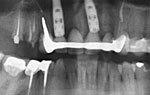

The zygoma implants are placed in the back section of the jaw approached within the mouth, along with the placement of one or more additional implants in the front region of your jaw. If the case is found too complicated or severe, two zygomatic implants may be placed on each side, which is known as Quad Zygoma.

When four zygoma implants are placed, two on each side it is called Quad zygoma. It provides high strength and excellent support for the restoration of teeth.